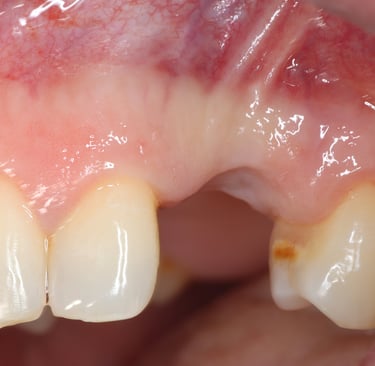

Chirurgie muco-gingivale

Traitement des récessions gingivales